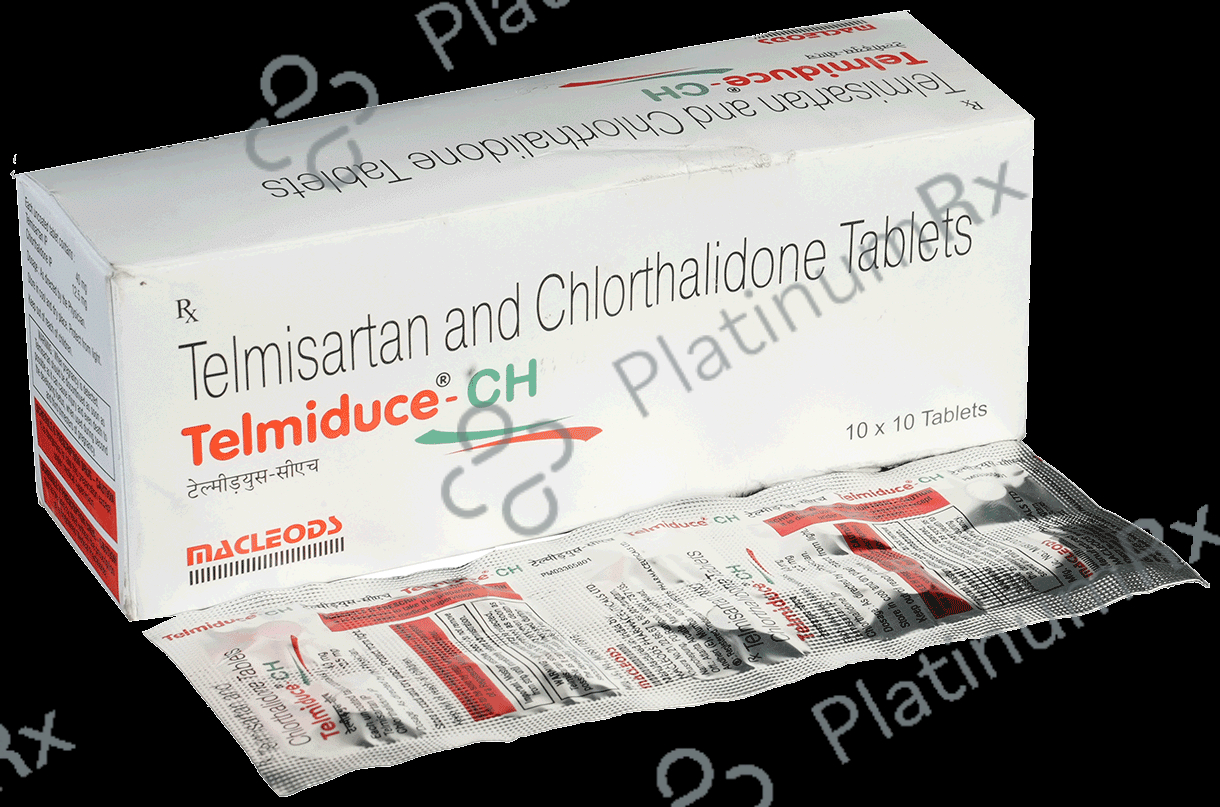

Telmiduce CH 40mg/12.5mg Tablet

Macleods Pharmaceuticals Pvt Ltd

Strip of 10 tablets

Telmiduce CH 40mg/12.5mg Tablet

Macleods Pharmaceuticals Pvt Ltd

Strip of 10 tablets

₹107.5

₹10.8 / Unit